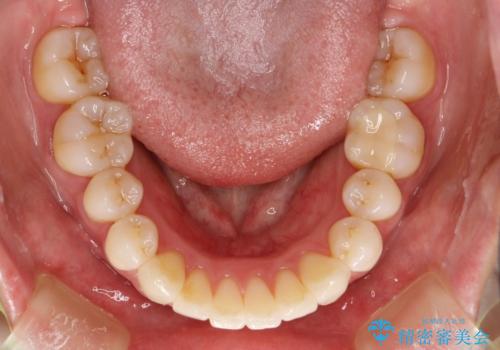

出っ歯をなおすために上顎の前から4番目の歯を抜歯して、引っ込めるのと、前から2番目の歯に通常の大きさのオールセラミックを装着して整った歯並びにすることにしました。

歯の大きさが通常と異なる場合は矯正治療で歯並びだけきれいにしても、整わないことがあります。

その場合はセラミックのかぶせ物を装着して歯の形を正常にすることで、さらに整った歯並びにすることができます。